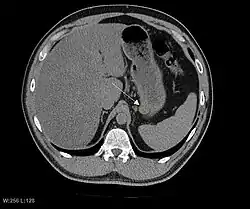

КТ-скан без контрастного усиления, демонстрирующий небольшую субсерозную ГИСО из задней стенки желудка (стрелка). Случайная находка.

Так как ГИСО происходят из мышечного слоя (который располагается глубже слизистого и подслизистого слоёв), небольшие ГИСО чаще визуализируются как подслизистое или внутристеночное объёмное образование. При исследовании желудочно-кишечного тракта с барием обычно выявляются ровные контуры образования, формирующие прямой или тупой угол со стенкой, что наблюдается и при любых других интрамуральных процессах. Поверхность слизистой интактна, за исключением случаев изъязвления, которые присутствуют при 50 % ГИСО. При КТ с контрастным усилением, небольшие ГИСО обычно визуализируются как интрамуральные образования с ровными, чёткими контурами и гомогенным контрастированием.

По мере роста опухоли, она может проецироваться снаружи от органа (экзофитный рост) и/или в просвете органа (интралюминальный рост); чаще всего ГИСО растут экзофитно, таким образом большая часть опухоли располагается в проекции брюшной полости. Если увеличение объёма опухоли опережает рост её кровоснабжения, опухоль может некротизироваться в толще, с формированием центральной зоны жидкостной плотности и кавитацией, что может приводить к изъязвлению и формированию соустья с полостью органа. В этом случае исследование с бариевой взвесью может демонстрировать газ, уровни газ/жидкость или депонирование контрастного препарата в этих областях.[17][18] При КТ с контрастным усилением крупные ГИСО выглядят негомогенно, в связи с неоднородностью структуры опухоли, обусловленной участками некроза, кровоизлияниями и полостями, что радиологически проявляется контрастированием опухоли преимущественно по периферии.[16]

Злокачественность может проявляться локальной инвазией и метастазами, обычно в печень, сальник и брюшину. Однако встречаются случаи метастазирования в кости, плевру, лёгкие и забрюшинное пространство. По сравнению с аденокарциномой желудка или лимфомой желудка/тонкой кишки, злокачественная лимфаденопатия при ГИСО не типична (<10 %).[16] При отсутствии метастазов радиологическими признаками злокачественности являются большие размеры опухоли (>5 cm), гетерогенное контрастирование после введения контрастного препарата и наличие изъязвлений.[3][16][22] Также явно злокачественное поведение (без учёта опухолей со злокачественным потенциалом) реже наблюдается при ГИСО желудка, с отношением доброкачественных опухолей к явно злокачественным 3-5:1.[3] Даже в случае наличия радиологических признаков злокачественности, следует учитывать, что они могут быть обусловлены другой опухолью; окончательный диагноз должен быть установлен иммуногистохимическим методом.